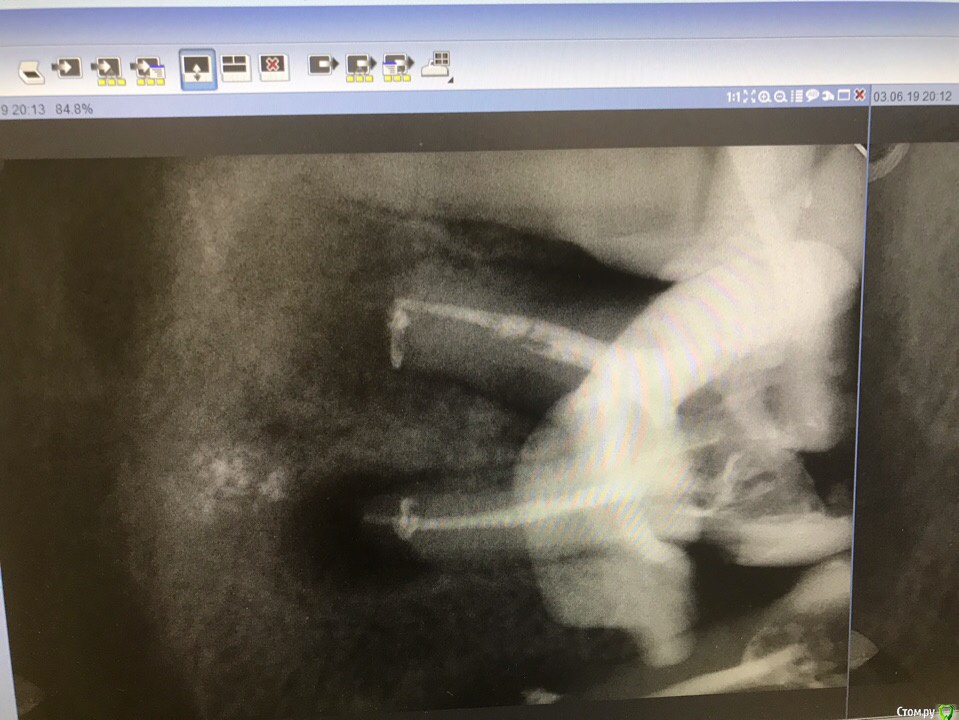

1586Doc Опубликовано 30 марта, 2019 Автор Поделиться Опубликовано 30 марта, 2019 (изменено) Еще немного работы45 зуб эндо и пломба и 46 зуб эндо и пломба на снимке справа Изменено 30 марта, 2019 пользователем 1586Doc Ссылка на комментарий